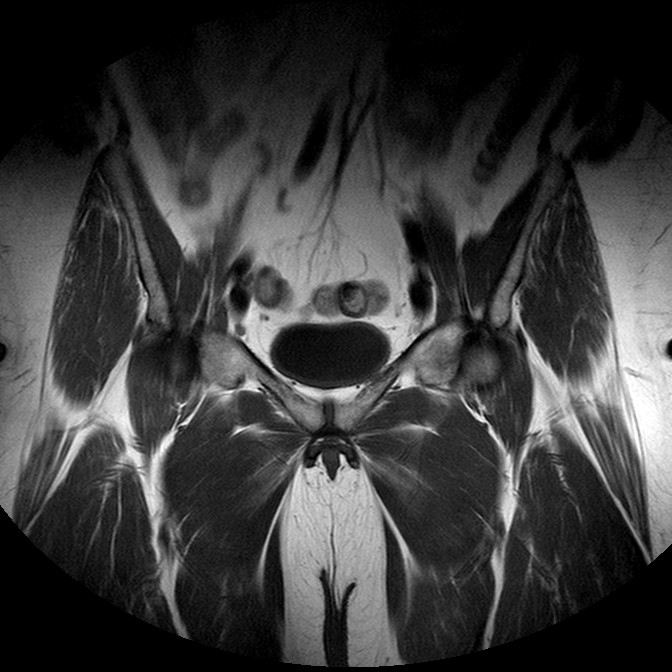

Esami: RMN BACINO

T1w TSE

Evidenti e simmetriche alterazioni osteofitosiche in regione coxo femorale con riduzione delle rime articolari. Degenerazione completa del cercine glenoideo. Non attuali segni di versamento articolare. Non segni di edema osseo che escludono attuale algodistrofia od osteonecrosi. Lieve e simmetrica riduzione del trofismo della muscolatura glutea.